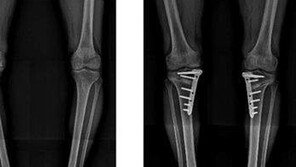

![[Health&Beauty]휜 다리 교정, 관절염 치료 병행하면 효과 커](https://dimg.donga.com/a/296/167/95/2/wps/NEWS/IMAGE/2014/12/16/68566052.1.jpg)

맞벌이인 딸 내외를 대신해 손자를 돌보고 있는 권모 씨(64·여)는 유치원에 다니는 손자의 말에 적잖은 충격을 받았다. “할머니 다리는 괴물다리”라며 놀림을 당한 것. 그렇지 않아도 O자 다리가 갈수록 심해져 신경이 쓰이던 참이라 마음이 아팠다. 무릎 통증까지 심해져 괴로워하던 권 씨…